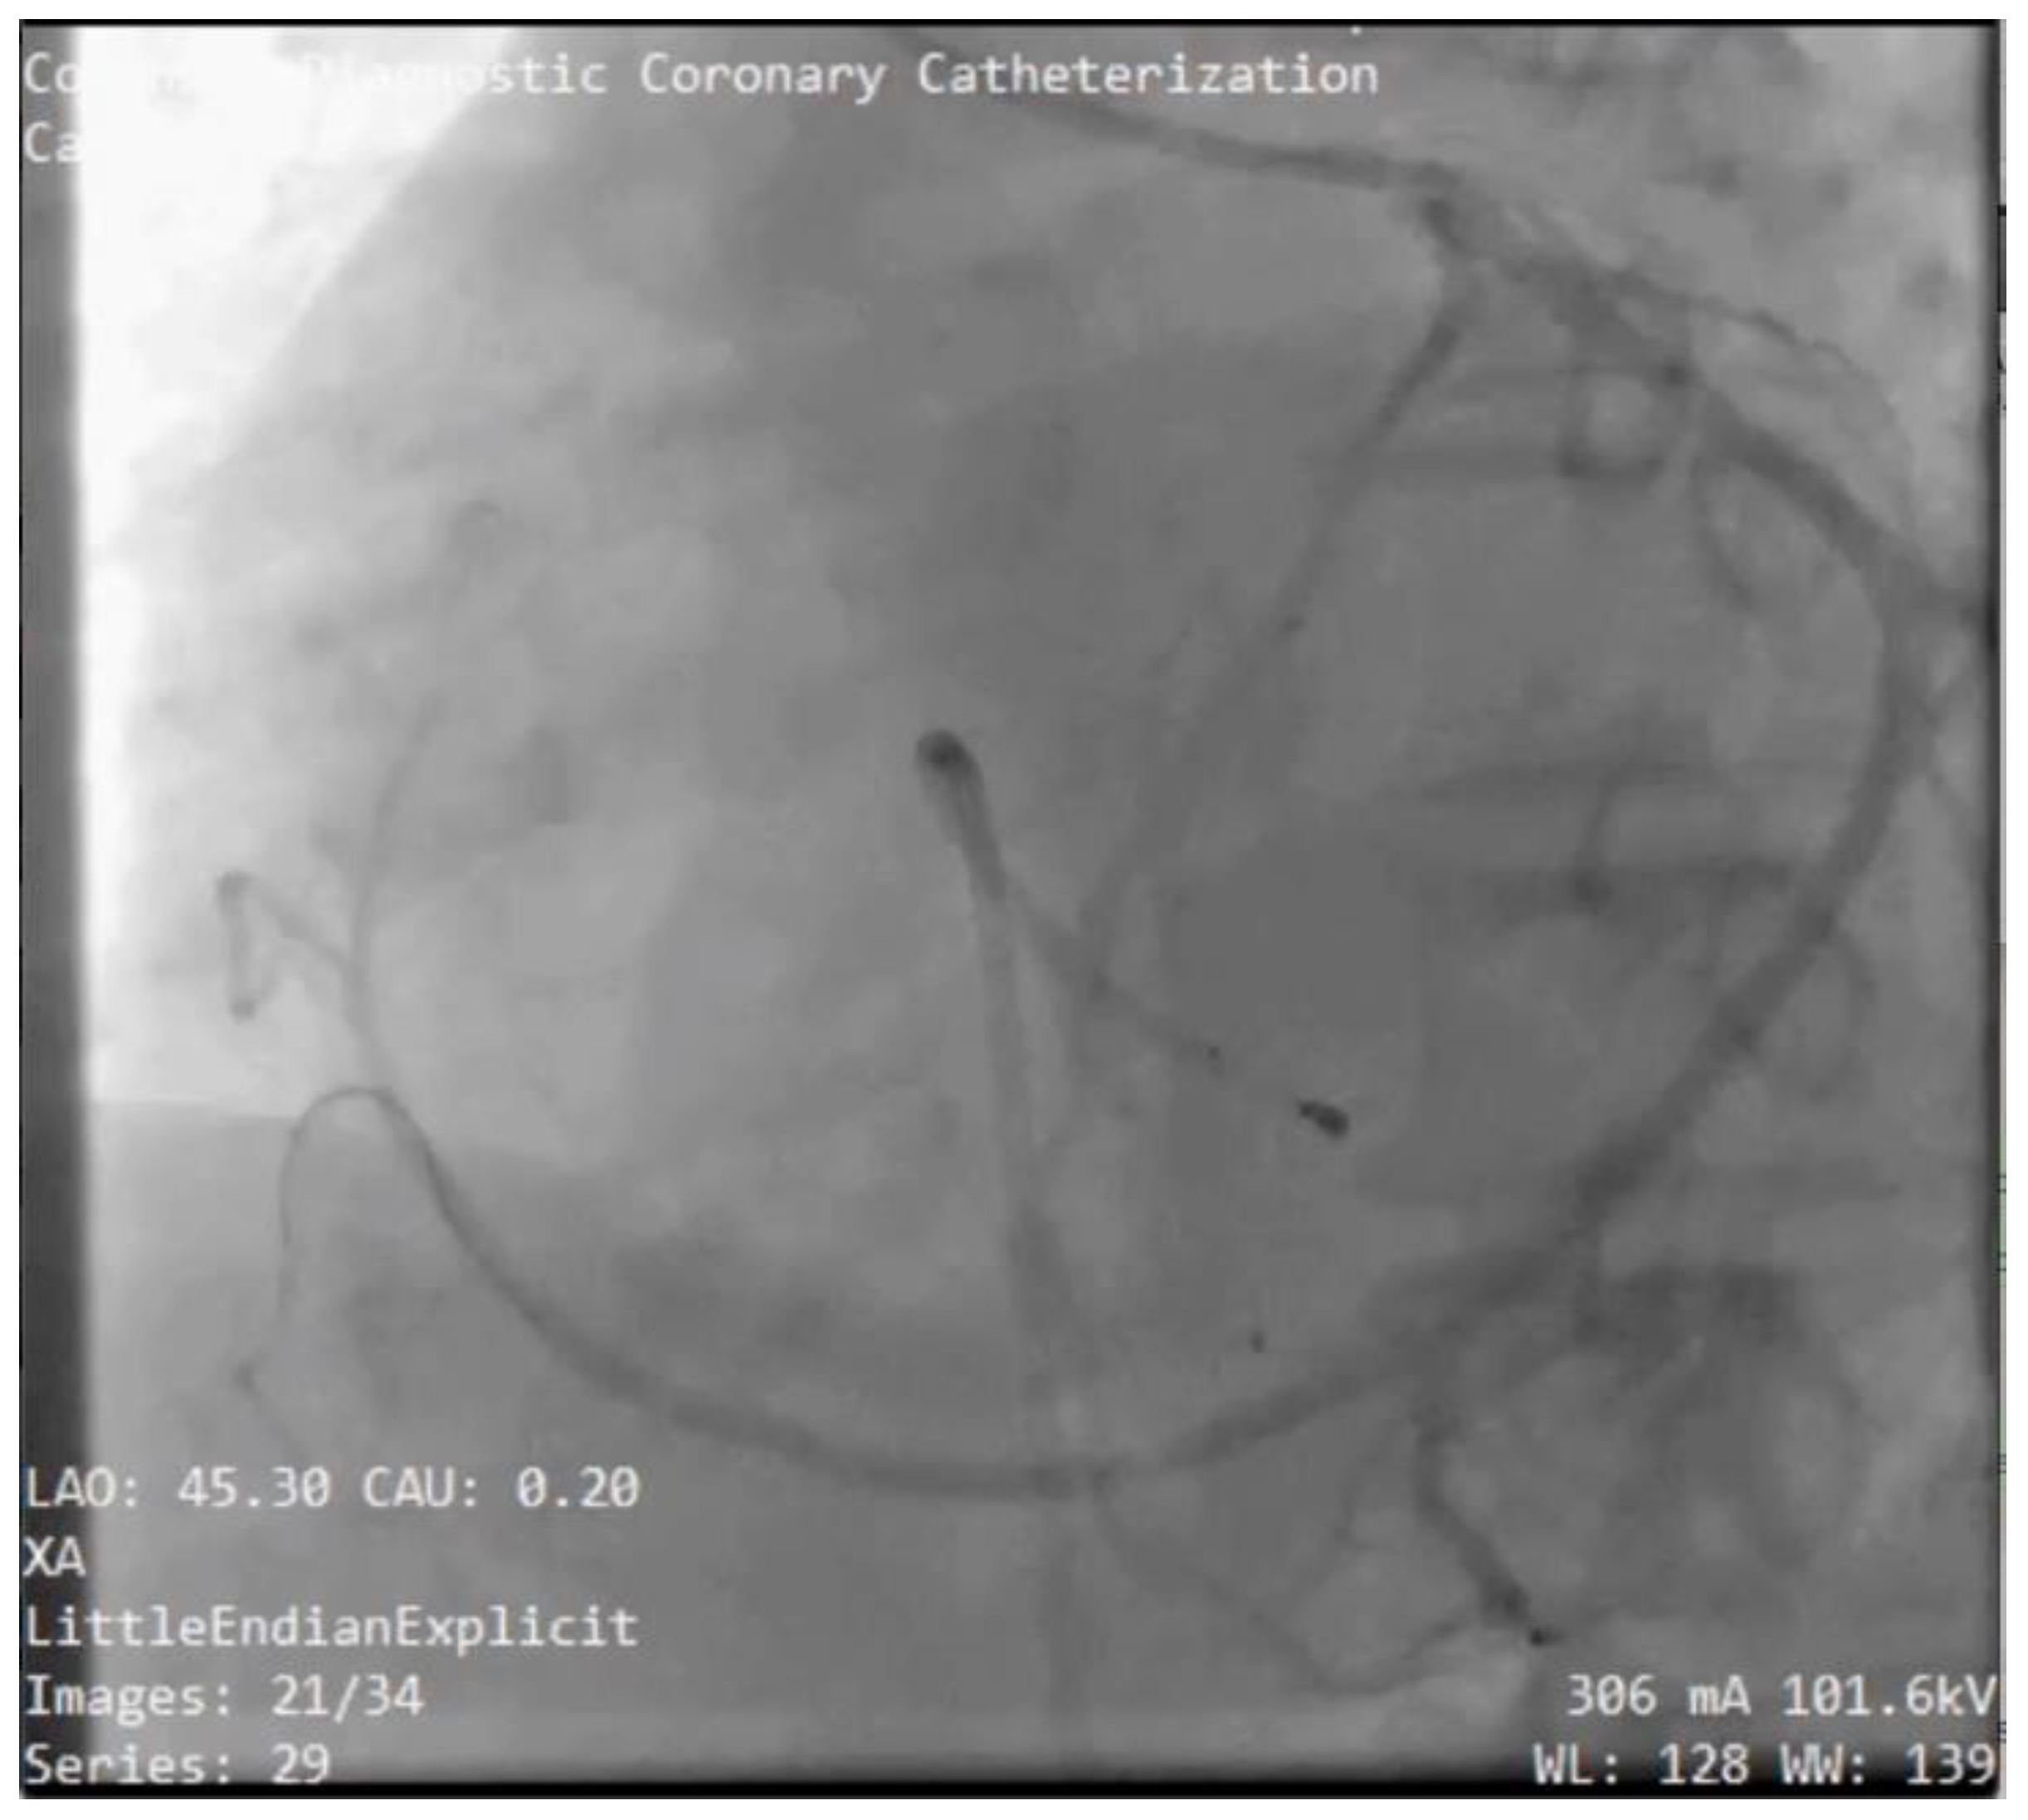

Figure 11. Case #3: The angiography LAO; CAU view shows the LAD feeds collaterals from septal branches to the distal left circumflex coronary artery (LCx) and total occlusion of the ostial LCx.